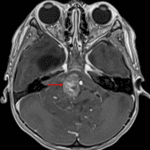

MRI

- Large, heterogeneously enhancing mass arising at the floor of the fourth ventricle and extending through the right greater than left foramina of Luschka and foramen of Magendie into the prepontine and premedullary cisterns and upper cervical spinal canal

- Extensive corresponding mass effect on the cerebellum, pons, medulla, and upper cervical spinal cord

- A few foci of internal susceptibility artifact likely represent calcification in correlation with the CT

- Encasement of the basilar and intradural vertebral arteries